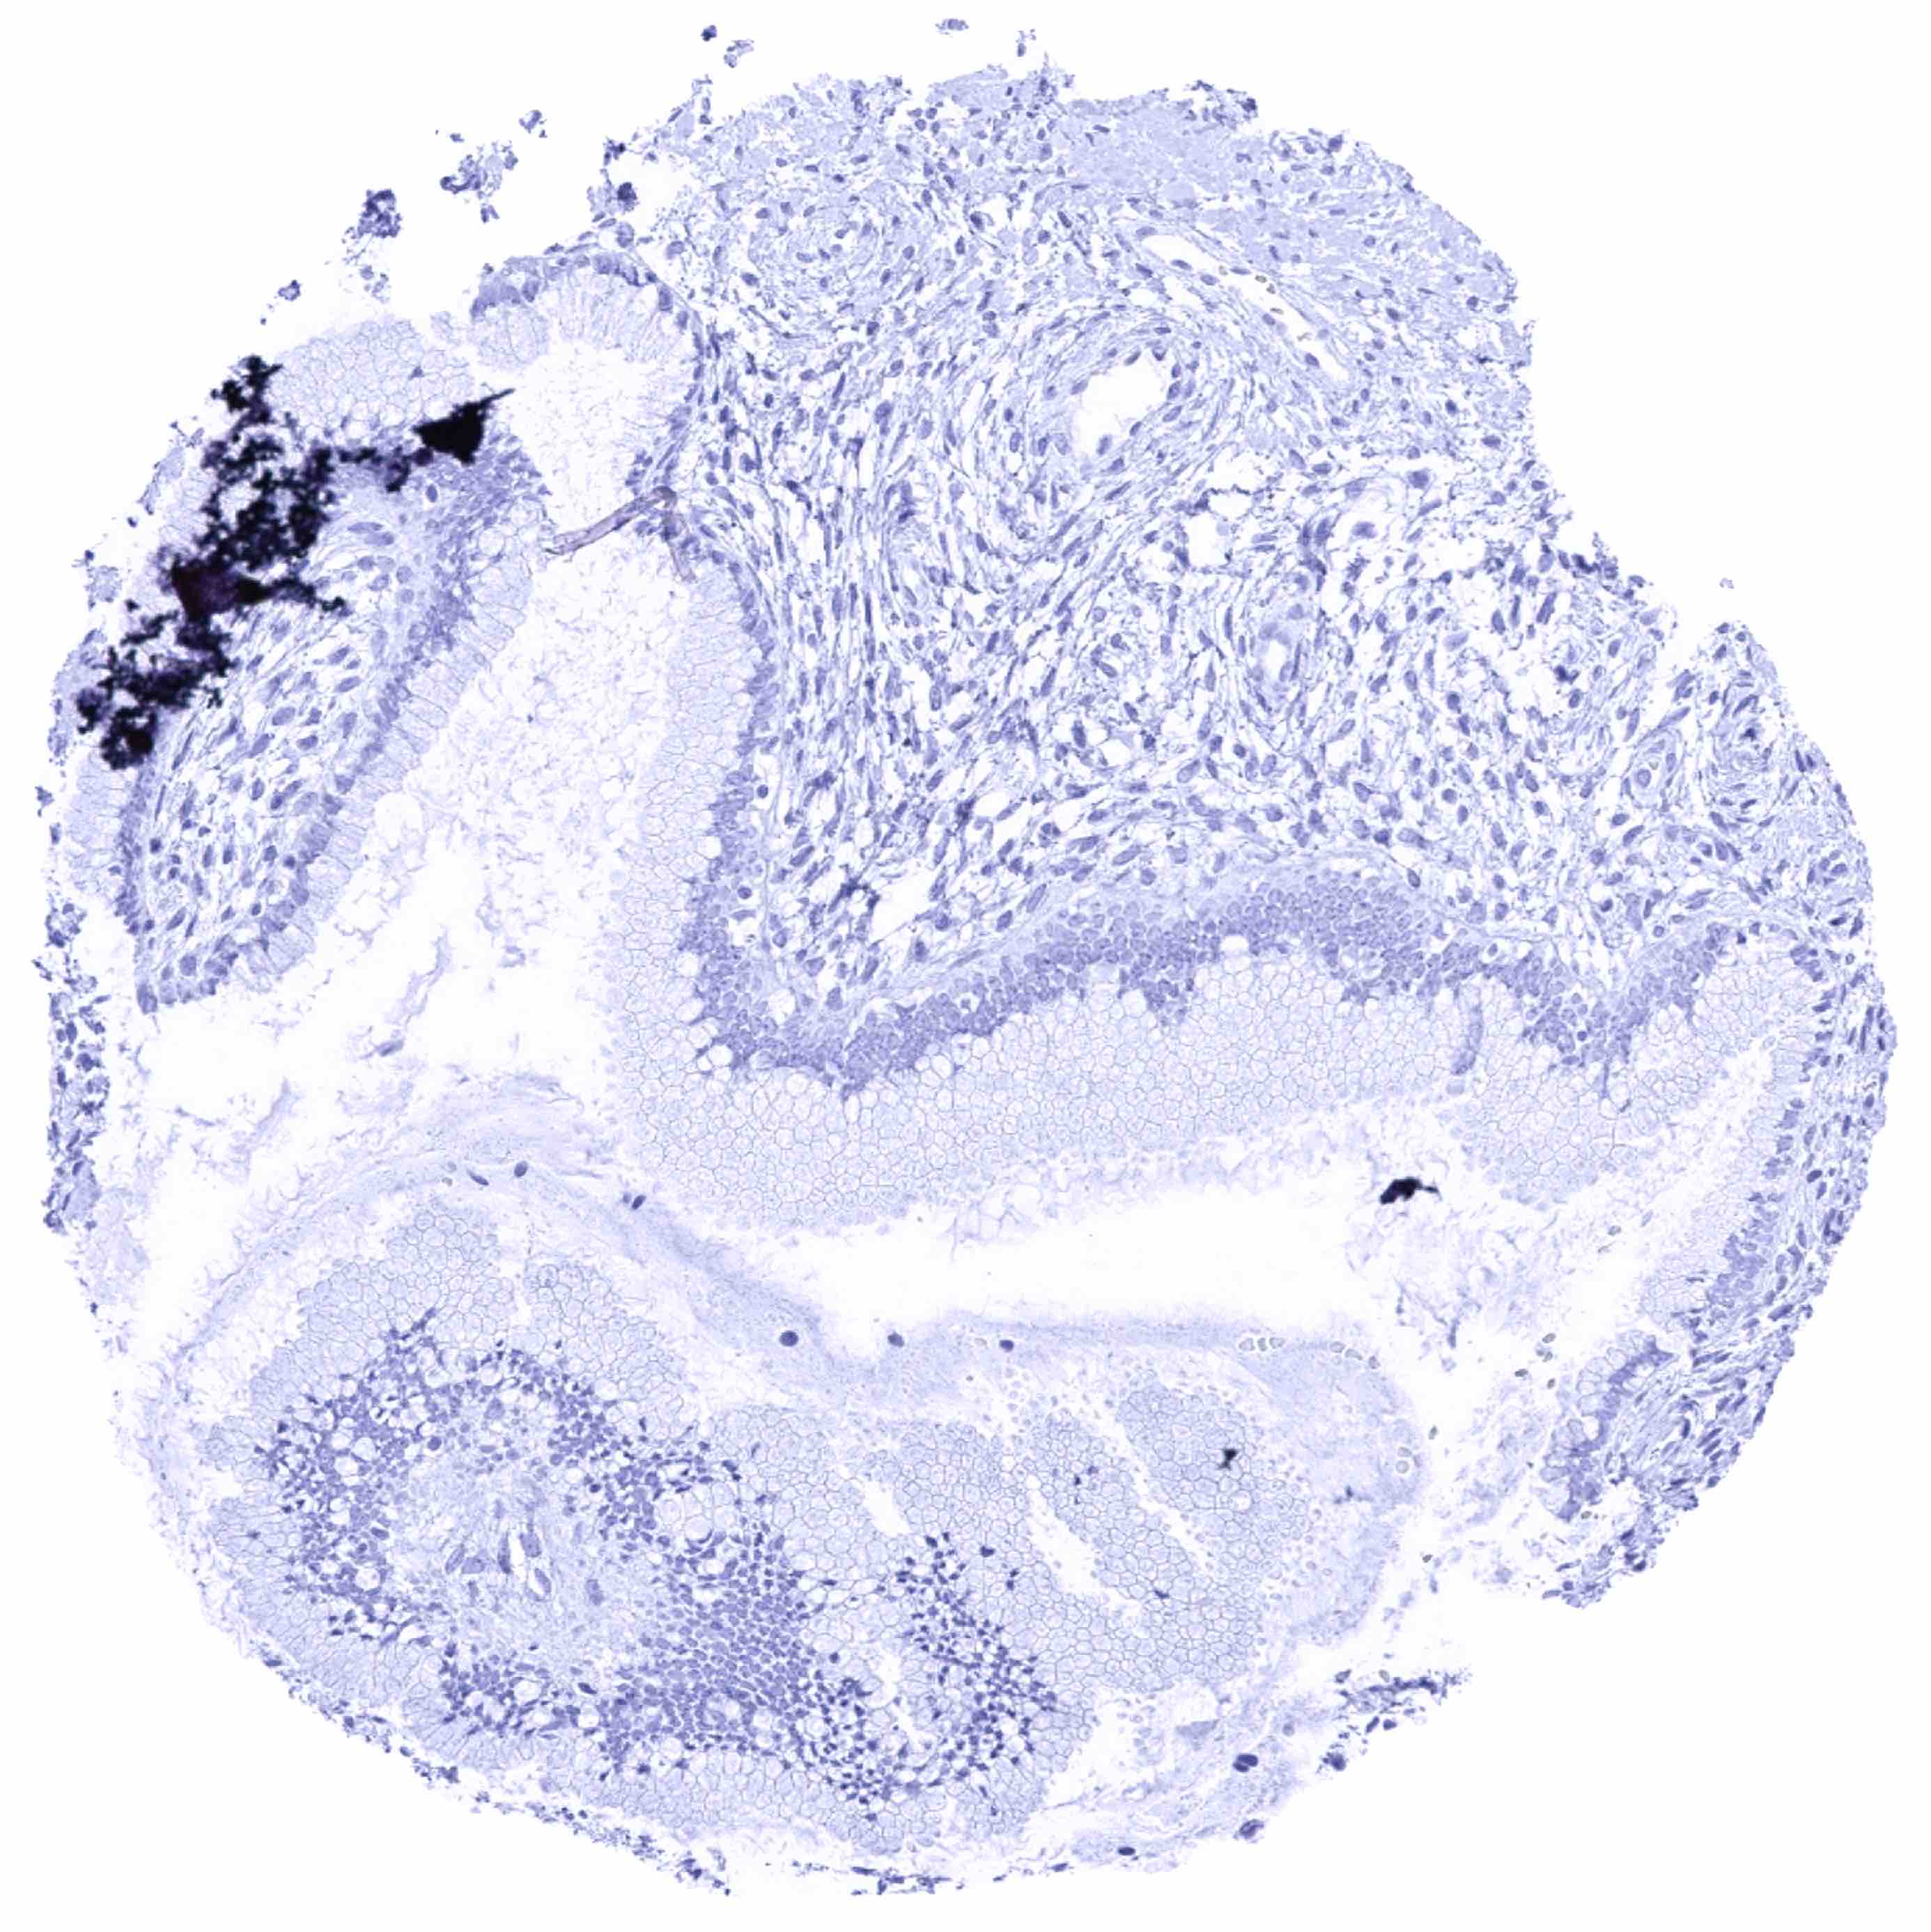

Tonsil